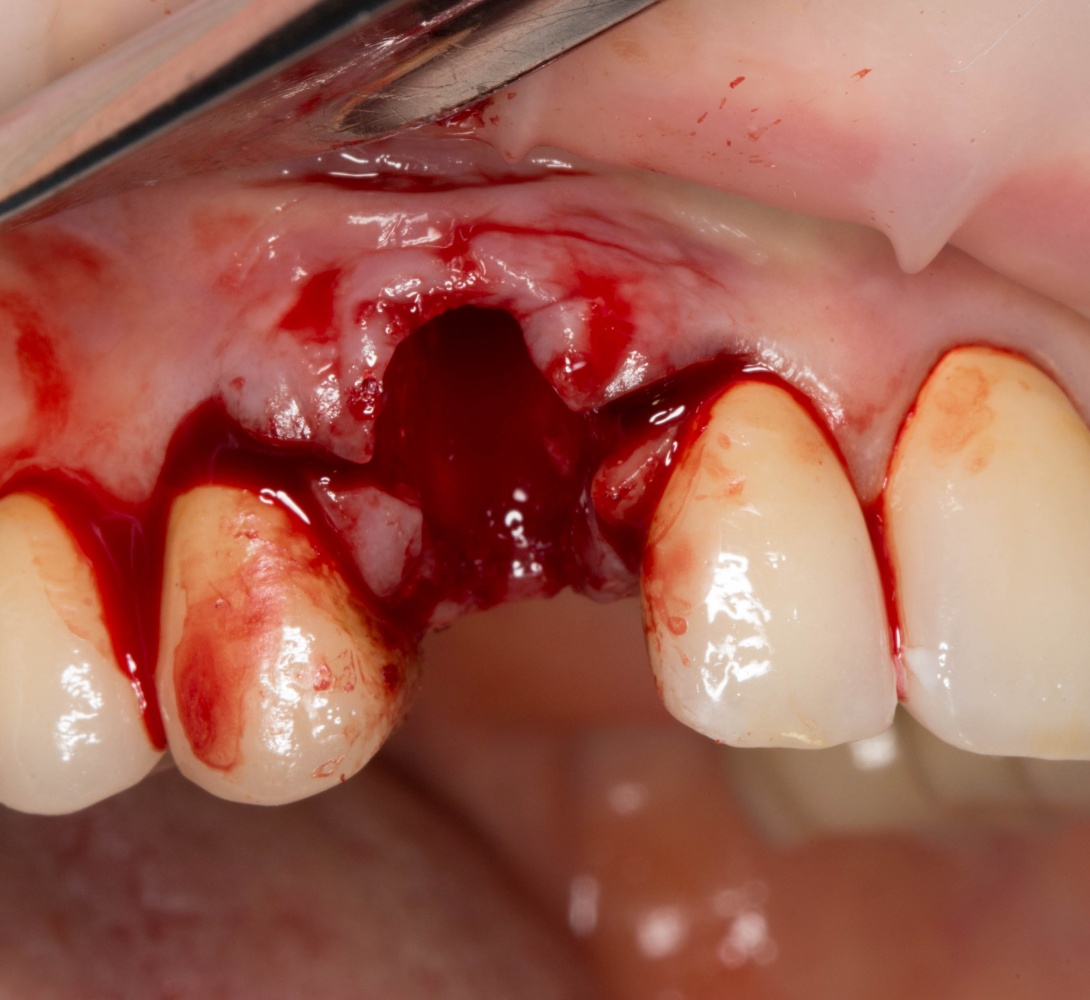

Рекомендации по установке имплантов. Для всех. Часть V.